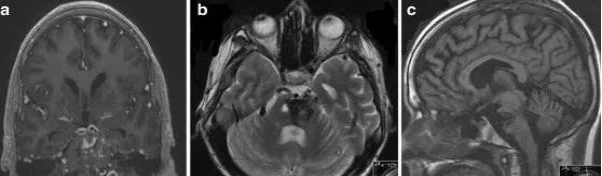

血管畸形有四种类型,动静脉畸形,海绵状血管瘤,毛细血管扩张和静脉发育性异常。实质性海绵状血管瘤MRI典型的表现为爆米花样、边界清晰、轮廓规整的复杂病变,中心区域由信号混杂灶组成,代表不同阶段的出血,其周见低信号环环绕,代表含铁血黄素沉积。

(图 A 为静脉血管瘤及海绵状血管瘤;图 B 为海绵状血管瘤(爆米花征);图 C 为毛细血管扩张;图 D 为动静脉畸形)

6、脑干发育静脉畸形:常见于20~50 岁;大多数无症状,有时与癫痫、头痛、神经功能缺损或脑积水相关,但很少出现破裂或出血。典型影像学表现:海蛇头。

7、脑干海绵状血管瘤:一次发病多在 30 岁左右,易出血(每年增加 2.4%~6%)及再出血(21%~60%),典型影像学表现:「桑葚样」或「爆米花样」。

8、脑干毛细血管扩张:大多数无症状,是否与临床表现相关不明确;病灶大部分位于脑桥,单一,小病灶(通常小于 2 cm),大多数在 T1 相正常,T2WI 等信号或稍高信号,均匀强化或点缀样强化;强化灶边界不规则,刷样改变,而并无特异性;特征性影像学表现为 T2*GE 序列毛细血管扩张。其它影像学表现包括:无占位效应,随访病灶稳定。

9、脑干动静脉畸形:原发性脑内动静脉畸形少见,常见20~30 岁,易出血,80%~90% 的患者因颅内出血而就诊,在脑干部位好发中脑,其次为脑桥及延髓;脑干部位 AVM 与颅内 AVM 影像学表现一致;异常扩张、发育血管结构,「流空」现象,有时因血管内高流速或血栓形成可呈高信号,AVM 破裂时可有出血征象。